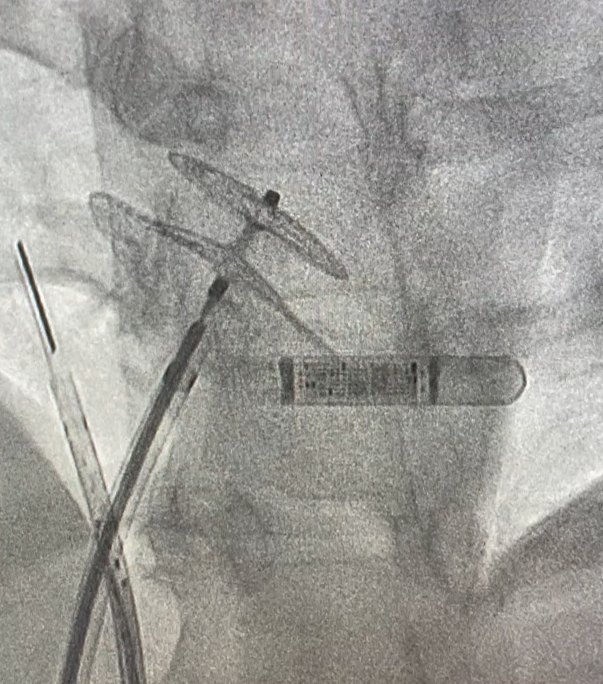

Fluoroscopy image showing closure of atrial septal defect with Amplatz device